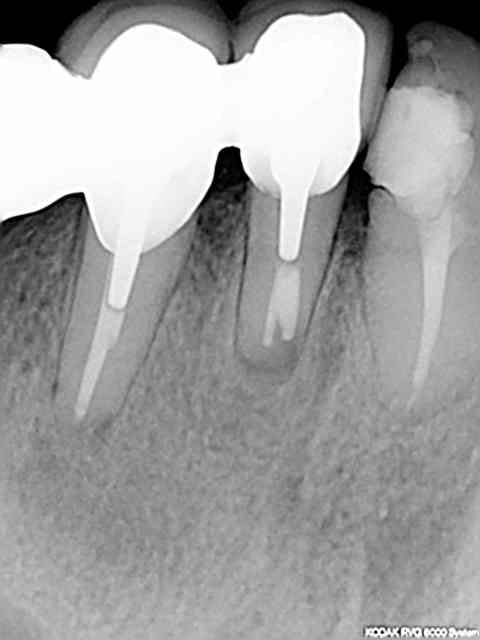

Image001 e0kg9q - Eugenol

je viens de voir votre post et vous mets une réponse en ligne avec quelques radios preop, postop, à 4 ans après et je vous dirai ce que j'ai mis pour obtenir ce résultat satisfaisant il me semble, par ailleurs vous me direz si en toute impartialité vous auriez opté pour la même option de tt ou si vous n'auriez pas fait l'exo et implanto.

à vous lire....